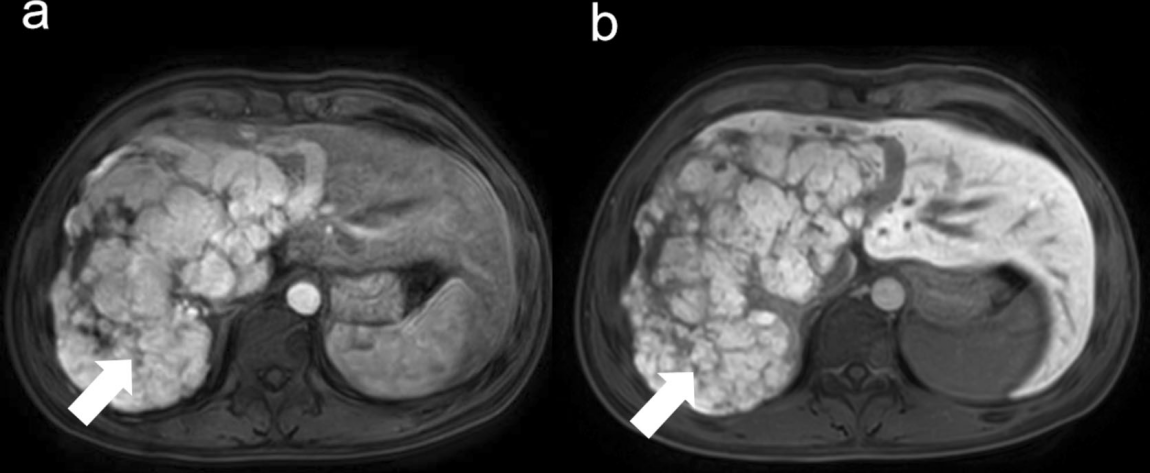

图为患者肝右叶不规则大结节(箭头所示)肿瘤大小为99 x154x174 mm

北京清华长庚医院1月13日电(通讯员 黄鑫 编辑 周汐遥)22岁的小星,在体检中发现巨大肝脏局灶性结节性增生(Focal Nodular Hyperplasia,FNH),病变大小已达99*154*174 mm,占据了整个肝脏右叶和小部分左肝,导致小星腹胀、纳差、肝功能异常。